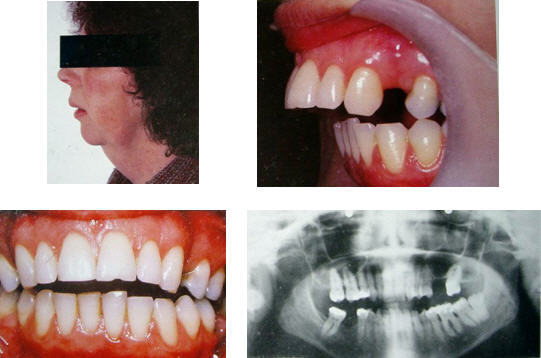

ภาวะข้อต่ออักเสบหลายข้อ

มีอาการแสดงทางคลินิก คือ อาการปวดในระยะเฉียบพลัน หรือกึ่งเฉียบพลัน

(subacute) อาจมีเสียงกรอบแกรบในข้อต่อ อ้าปากได้น้อยเนื่องจากอาการปวด

หรือมีการเสื่อมสภาพ (degeneration) ภาพถ่ายรังสีข้อต่อขากรรไกรแสดงถึงการเปลี่ยนแปลงของกระดูกข้อต่อ

และหากมีการละลายของคอนดายล์ทั้งสองข้างก็ทำให้เกิดภาวะฟันหน้าสบเปิด

(anterior openbite) ผู้ป่วยส่วนใหญ่มีแพทย์ประจำตัวดูแลเรื่องภาวะข้อต่ออักเสบหลายข้ออยู่แล้ว

แต่อาจจะส่งปรึกษาทันตแพทย์ในกรณีที่มีอาการที่ข้อต่อขากรรไกรร่วมด้วย

การวินิจฉัยที่ดีที่สุดคือการตรวจซีรัม (serology test) <<คลิกกลับตาราง